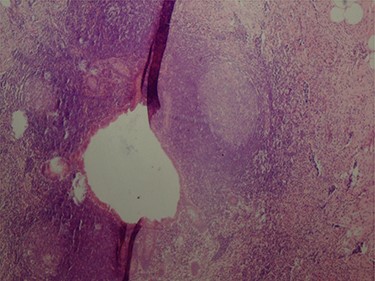

The pathologic examination showed an appendix of 6 × 1.5 cm with a constricted lumen suggesting appendiceal obstruction (Fig. 1). Microscopic examination showed subserosal deciduosis with large polygonal decidual cells, eosinophilic abundant cytoplasm and round nuclei with prominent nucleoli. A hyperplasic lymphoid reaction was found in the submucosa and mucosa (Figs 2 and 3).